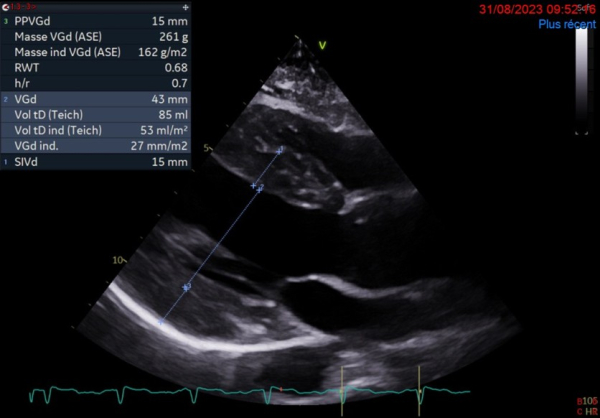

L'ETT montre :

- Dilatation modérée du VG. FEVG à 30%

- Cardiopathie hypertrophique sévère excentrique

- Flux mitral restrictif

- Ventricule droit non dilaté

- Paroi libre épaissie

- Minime épanchement péricardique circonférentiel

Figure 1